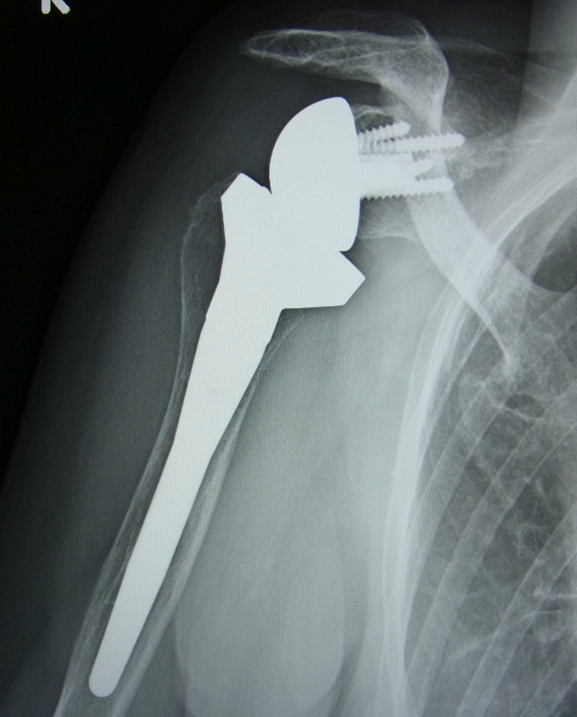

リバース型人工肩関節は腱板が無くなった患者さんのために設計された人工肩関節です。人工関節の部品であるボールとソケットが従来の人工関節とは逆さまにデザインされています。

手術で治せない腱板断裂の患者さんにはリバース型人工肩関節置換術が有効です。腕が全く挙上できない状態の患者さんにこのタイプの人工関節を設置する事により痛みや動きが改善する事があります。

まれに、広背筋腱移行術を併用したリバース型人工関節置換術が行われる事もあります。

リバース型人工関節のレントゲン。修復できない腱板断裂の患者さんのために設計されたものです。。